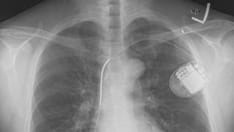

Whiplash injuries cause traction on the upper cervical spine and atlantooccipital junction. Atlantooccipital separation or injuries of the atlantooccipital apparatus can result in devastating injuries to the brainstem or upper cervical cord, resulting in rapid death (see the radiograph below). Complete separation is not necessary. Laxity in this region from ligamentous tearing can be enough to cause injury to the medulla oblongata. Occasionally, microscopic examination of the brainstem may be necessary to document hemorrhage. Transient mid and lower cervical spine separation can result in traction either on the spinal cord at that point or farther up, resulting in partial or complete separation of the pontomedullary junction.

Atlantooccipital separation. Note the increased space between C1 and the base of the skull.